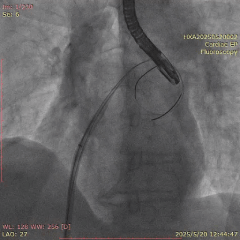

在经股静脉途径的TEER手术时,房间隔穿刺是一个很重要的基础步骤。有时候房间隔组织较韧较厚(多见于房间隔短穿刺位置需要靠后,或者外科房间隔修补术后),穿刺针通过之后要通过导引大鞘(GC)存在着较大困难,若强行推送大鞘可引起房间隔撕裂到左心房顶引起灾难性心包填塞。传统做法时使用外周球囊对房间隔进行扩张,但是不是每个导管室都常规配备外周球囊,且使用过大球囊仍可引起房间隔撕裂风险。我们提供了一种更简洁的方式,即使用导引鞘内芯和房间隔穿刺鞘两个管子(双管齐下)同时扩张房间隔穿刺口,再推送导引大鞘通过房间隔,无需额外器械,操作简单高效且安全(图1-4)。

图4. 顺利送入导引鞘通过房间隔